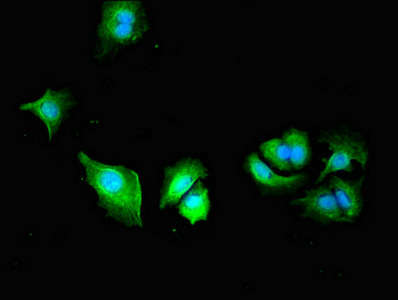

Immunofluorescent analysis of MCF-7 cells using CSB-PA018206LA01HU at dilution of 1:100 and Alexa Fluor 488-congugated AffiniPure Goat Anti-Rabbit IgG(H+L)